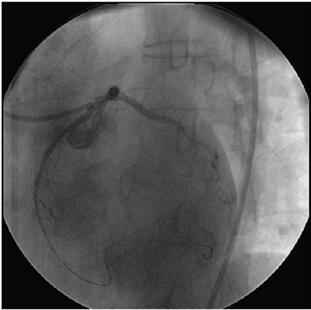

L AD 行PCI 术(图058‐4~图058‐7):送入7F XB 3﹒5 指引导管至左冠口,根据此前造影影像,循管送入Runthrough NS 导丝至LAD 远端,再送入Fiel der 导丝至LCX 远端,沿L AD导丝送入1.5mm×15mm 球囊(Ryujin)定位于LAD 中段病变处,以20at m×20s 多次扩张,循管送入2.5mm×33mm 药物支架(Firebird 2)定位于LAD 中段病变处,以(8~10)at m×10s释放,复查造影见病变覆盖良好,局部无残余狭窄,再送入3.0mm×13mm 药物支架(Firebird 2)定位于LAD 中段病变处,以18at m×180s 释放,两支架部分重叠,复查造影见病变覆盖良好,局部无残余狭窄,沿LAD 导丝送入3.0mm×18mm 药物支架(Firebird 2)定位于LAD 近中段病变处,以18at m×20s 释放,复查造影见病变覆盖良好,局部无残余狭窄,再送入3.5mm×29mm药物支架(Firebird 2)定位于L AD 开口后,以12at m×16s 释放,复查造影见病变覆盖良好,局部无残余狭窄,循管送入另一条Runthrough NS 导丝替换原LCX 导丝,沿LCX 导丝送入3.5mm×23mm 药物支架(Firebird2),支架跨越L M‐LCX 病变,以(12~14)at m×14s 释放,支架球囊定位于支架前后,以(12~14)at m×18s 多次后扩张,沿LAD 导丝送入4.0mm×12mm 球囊(Monorail),沿LCX 导丝送入3.5mm×12 mm 球囊(Monorail),同时以12at m 行Balloon Kissing 两次,复查造影(图058‐8~图058‐10)见病变覆盖良好,局部无残余狭窄,远端血流TI MI 3 级。

图058‐9 对吻扩张

图058‐10 手术结束